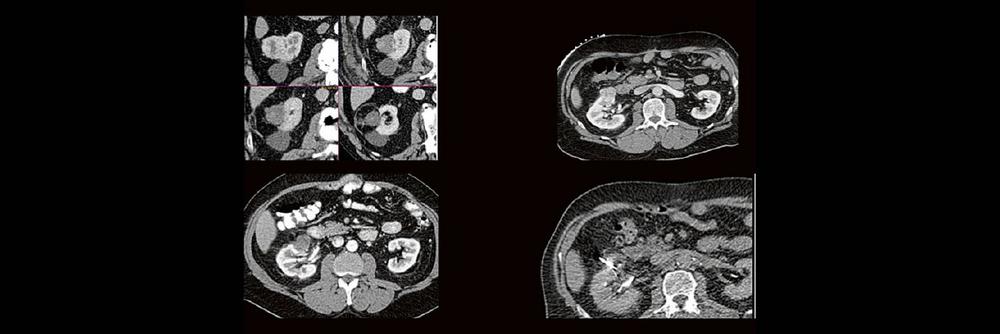

Die Anwendung von ablativen Verfahren hat sich in der klinischen Praxis etabliert. Nierentumoren bieten sich für den Einsatz von RFA und Mikrowelle an. Im Dietrich Bonhoeffer Klinikum Neubrandenburg blicken wir auf 15 Jahre Erfahrung mit mehr als 100 RFA/Mikrowellenablationen von Nierentumoren zurück. Im Vortrag werden die eigenen Erfahrungen und Ergebnisse vorgestellt.

Dabei wird auf die Indikationsstellung, Vorbereitung, Durchführung, Nachuntersuchungsintervall, Komplikationen und Erfolgsrate eingegangen.

Back to the roots! Gute Kenntnisse der Anatomie sind der Schlüssel zur guten Planung, Durchführung und richtigen Diagnosestellung im CT des Abdomens. Lernen sie unverkrampft

• richtiges Kontrastmittel-Timing im Bild erkennen

• Anatomie in Pathologie übersetzen

Haben Sie es erkannt? Probieren Sie selbst im lockeren Fallquiz zum mitraten.